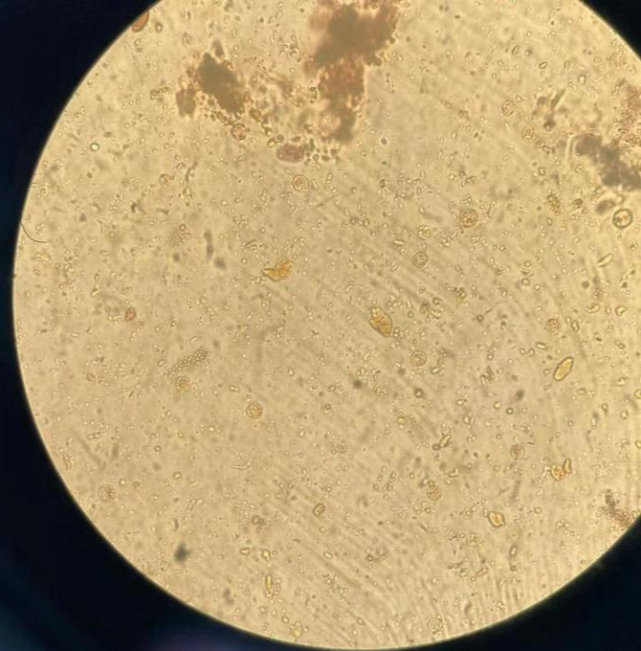

图1 湿片直接镜检的人芽囊原虫

虫体中等大小,直径约10-13微米,圆形,胞膜较薄,透明,内含一个较大空泡,与胞膜之间可见一些圆形颗粒(核或其他细胞器)